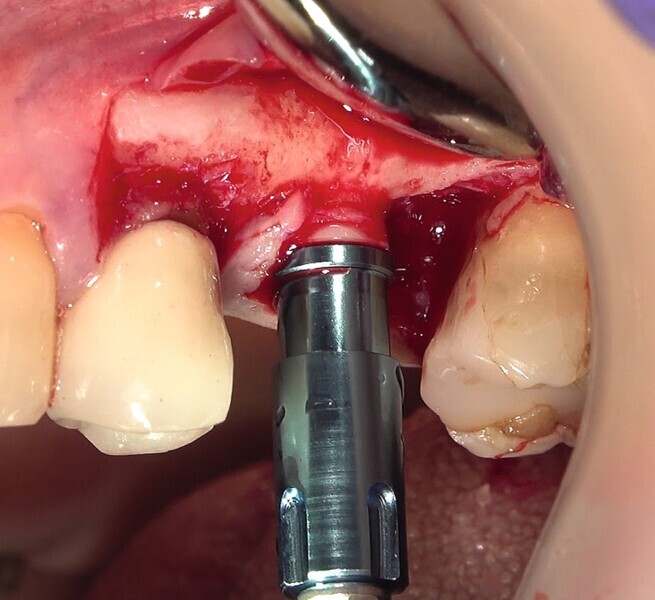

Fig. 6 : Insertion de l’implant.

Fig. 7 : Insertion de l’implant.

La première phase du traitement implantaire a consisté à extraire la dent et à préserver l’alvéole au moyen d’une allogreffe et d’une membrane de collagène. Six mois après, l’os régénéré a permis de procéder à la seconde phase du traitement comportant la pose d’un implant deux pièces en céramique (Figs. 1–11).